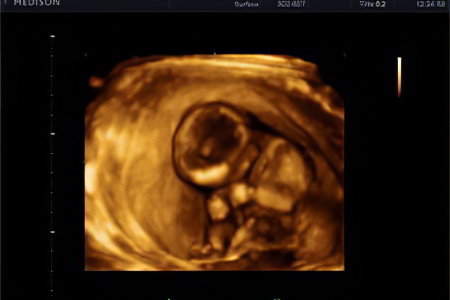

Что показывает УЗИ?

Если ваш акушер-гинеколог еще не назначил первое плановое ультразвуковое исследование для оценки состояния плода, сделайте это. Оптимальный период для УЗИ — с 10 по 14 неделю беременности.

Во время исследования можно получить следующие данные:

• Срок беременности;

• Предполагаемая дата родов;

• Состояние матки и плаценты;

• Количество плодов;

• Размер плода, его активность и особенности развития;

• Наличие факторов, указывающих на хромосомные аномалии.

На данном этапе можно выявить возможные пороки развития плода, поэтому ультразвуковое исследование является частью скрининга, который проводится в каждом триместре беременности.